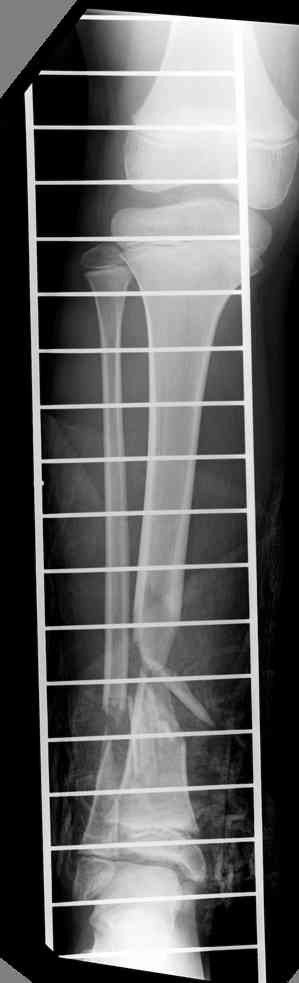

Пациент 19 лет, производственная травма, придавлен тяжелой плитой. Политравма (ISS 21).

1 - рентгенограмма (прошу прощения за качество) при поступлении;

2 - внешний вид голени;

Произведено ПХО, acute shortening (5 см), фиксация стержневым аппаратом Hoffman.